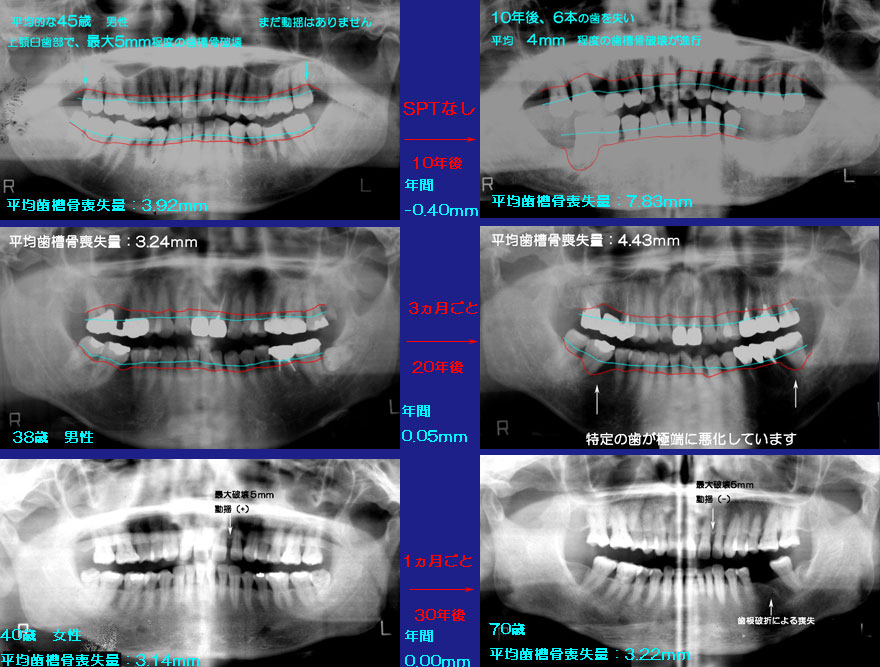

ピンクの帯が平均的な人の歯槽骨喪失パターンです。最初は、ゆっくりとしたスピードで破壊されていきますが、4mm程度 を超えると急速に破壊が進み、次々と歯を失っていきます。

モデルケースとして、平均4mm程度(中程度)の歯槽骨を失った40歳くらいの人の場合。

何もしないと、年間0.4mmのスピードで歯槽骨が破壊されていきます。10年間で約4mmです。

ところが毎月ケアをすると、10年経っても、20年経ってもほとんど破壊されません。

ちなみに3カ月ごとにケアを行うと、年間0.05mm程度の破壊が進み、20年間で1mm程度の破壊が進みます。